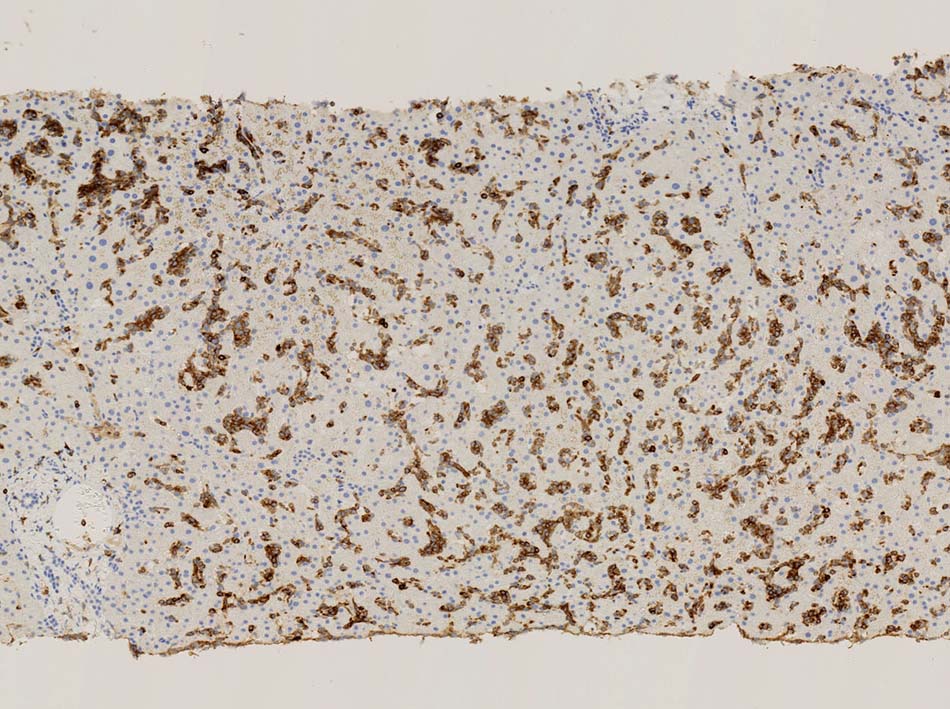

類洞内で増殖する腫瘍細胞はCD3+, CD7+のT-cellであるがCD5発現が弱く, 異常なT-cellである.

CD4は類洞内皮/macrophageの一部が陽性であるが, 類洞内腫瘍細胞の多くは陰性を示す(陽性と間違えないこと). CD8陰性. CD20陽性リンパ球はごく少ない.

TIA1は陽性であるが, granzymeBは陰性細胞が多い.